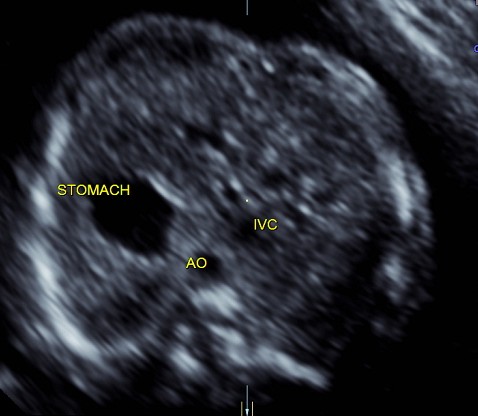

the following two pictures establish the normal situs